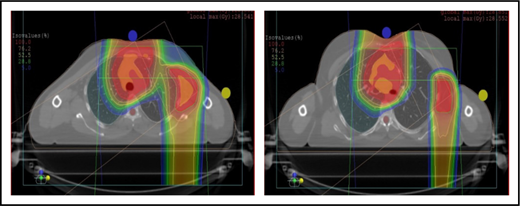

A 4D CT scan can help to establish the extent of respiration-induced anatomic motion and the appropriate ITV expansion. However, this introduces an additional uncertainty; to mitigate the latter, the radiation volume has to be increased. Thus, use of DIBH is ideal to reduce the motion of the mediastinum and its respiration-dependent change in shape (thinner during inspiration, wider during free breathing) (Figure 7).59 It is accomplished by acquisition of the anatomical data in a fixed respiratory phase. DIBH can have the additional benefit of displacing the heart inferiorly, as well as expanding the lungs away from the target, potentially reducing the dose received by these OARs.

Use of DIBH can help to manage some of the uncertainties associated with the use of proton therapy. Compared with free breathing (right panel), DIBH expands the lungs, moves the heart downward, and causes the mediastinum to become thinner (left panel).